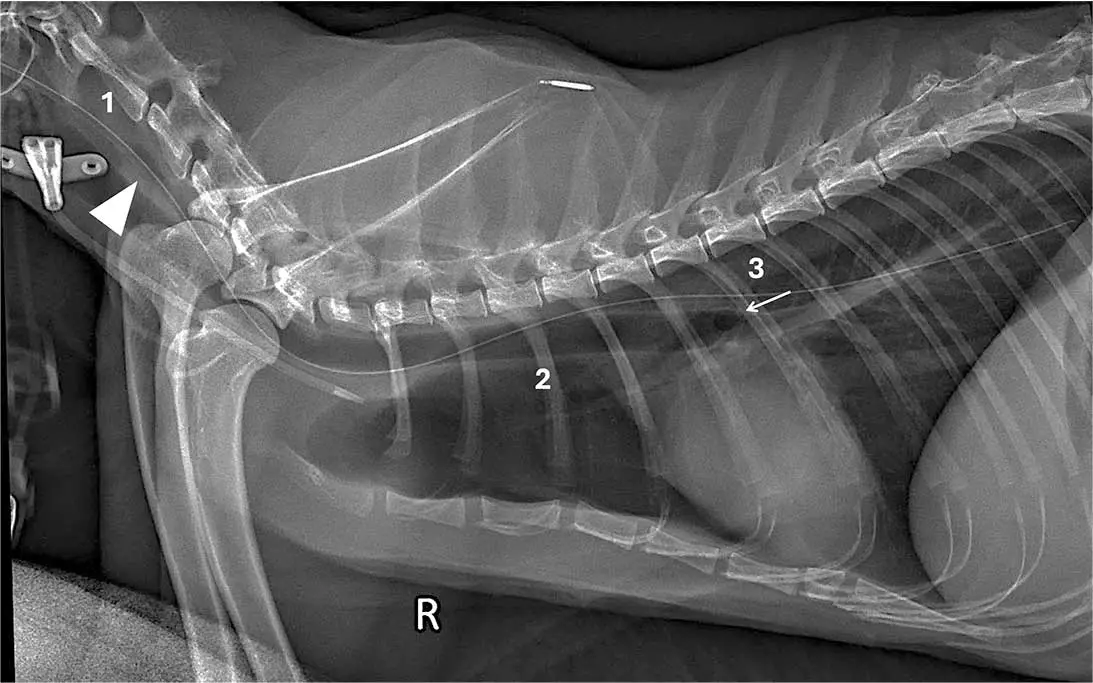

Case five

This lateral cervical and thoracic radiograph of a dog includes the larynx (Figure 5).

The feeding tube passes through the laryngeal lumen (1; arrowhead) and is superimposed over the nasopharynx, laryngopharynx and tracheal lumen (2), and it does not reach the carina (3; arrow). As the tube fails to reach the carina, inclusion of the larynx is essential to increase confidence in tube localisation.

Interpretation. Incorrect tracheal placement. Criteria one and two are not met, as the tube does not pass dorsal to the cricoid cartilage lamina, and completely overlaps the tracheal lumen throughout its course.

Criterion three cannot be used because the tube does not reach the carina. The tube was immediately removed and correctly repositioned.